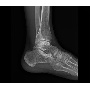

Klinikai esetek